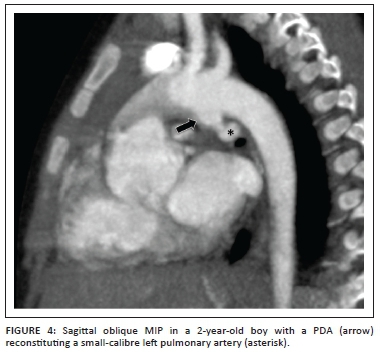

Branch pulmonary arteries and MAPCAs

The variability in surgical management of TOF is frequently because of the diverse arrangement of the pulmonary arterial anatomy and the source of pulmonary artery blood supply. TOF with pulmonary atresia (TOF-PA) is a more severe variant that accounts for 20.3% of TOF13 where the arrangement of the pulmonary arteries may vary from well-formed, confluent pulmonary arteries (pulmonary arteries in free communication) supplied by the patent ductus arteriosus (Figure 4), to absence of the pulmonary valve and the native pulmonary arteries, with MAPCAs providing all the pulmonary supply. The anatomy of the native pulmonary arteries and vessels of supply must be clearly established in order to plan corrective surgery.11